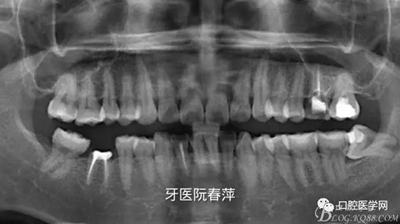

(5)X光片檢查:全景片看到25齲壞未近髓,26根管充填材料良好,27根管無充填材料,根尖區(qū)未見低密度影。

全景片如下圖